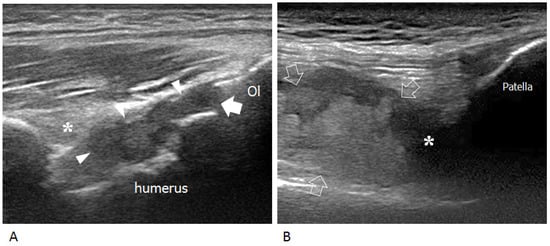

2. Ultrasound and Disease Activity

3. Ultrasound and Osteochondral Damage